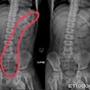

[新聞] 男童唇發紫送急診!照X光「屎塞到胸部」

46Fhatephubbing: 從小開發頂到肺42.79.19.115 10/29 11:29